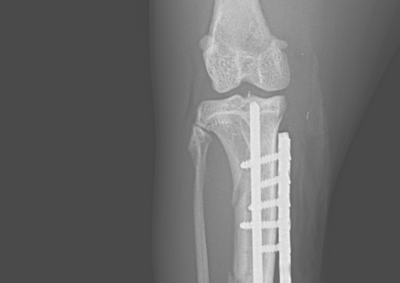

整形外科 注意 ボタンをクリックした先に、治療中および手術中の画像が説明で使用されている場合がございます。 そのような画像に弱い方は閲覧なさらないようお願いいたします。 整形外科 若齢犬の橈骨固定術 #271 整形外科 前十字靭帯断裂(中型犬)に対するCBLO #255 整形外科 超小型犬に対する上腕骨遠位Y字骨折 整形外科 大型犬の前十字靭帯疾患(慢性経過)に対するCBLO #254 整形外科 橈骨固定術 #270 整形外科 膝蓋骨内方脱臼に対する人工滑車置換術 PGR #23 整形外科 犬の前十字靭帯(疾患)部分断裂に対するCBLO #253 整形外科 犬の前十字靭帯断裂に対するCBLO #252 整形外科 膝蓋骨内方脱臼+前十字靭帯断裂に対するPGR#22・LSS 整形外科 大腿骨骨折 整形外科 橈骨固定術 #269 整形外科 上腕骨外顆骨折の癒合不全 123456> 症例カテゴリー 放射線治療整形外科軟部組織外科脳神経外科内科腫瘍外科救急・集中治療リハビリテーション科腫瘍内科内視鏡科脳神経科呼吸器外科中医・漢方猫の腎移植循環器科